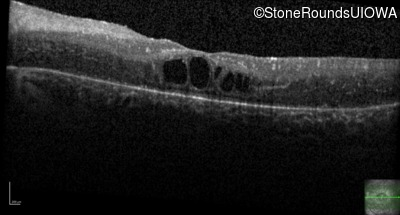

Age at visit: 17 years

This 17 year old female feels that the vision in her right eye has worsened since her cataract surgery 8 weeks ago.